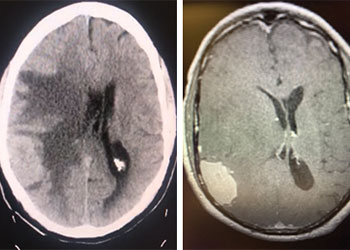

Urgent Cerebral Angiography confirmed a 5 mm posteriorly projecting aneurysm of the Basilar Artery Apex (Figure 2 A, B). Based on the location, morphology, and posterior projection, we decided to proceed to coil embolization of this high-risk aneurysm to prevent catastrophic re-bleeding and afford us the opportunity to maximize critical care for this patient during his hospital course. In this aneurysm, the dome-neck ratio was favorable from primary coiling, which was successfully performed resulting in near-complete embolization of the aneurysm (Figure 3 A, B). After 2 weeks of continued critical current l, endovascular, and neurosurgical care for complications of subarachnoid hemorrhage, including vasospasm and hydrocephalous, he was able to make a complete recovery and ultimately discharged home to complete his recovery, having regained all neurologic functions and activities of independent daily living and planning a return to work as an executive professional in the near future.

Figure 3: A) Initial Coil placement in Aneurysm dome B) Final AP and C) Lateral DSA demonstrating near complete obliteration of the ruptured aneurysm